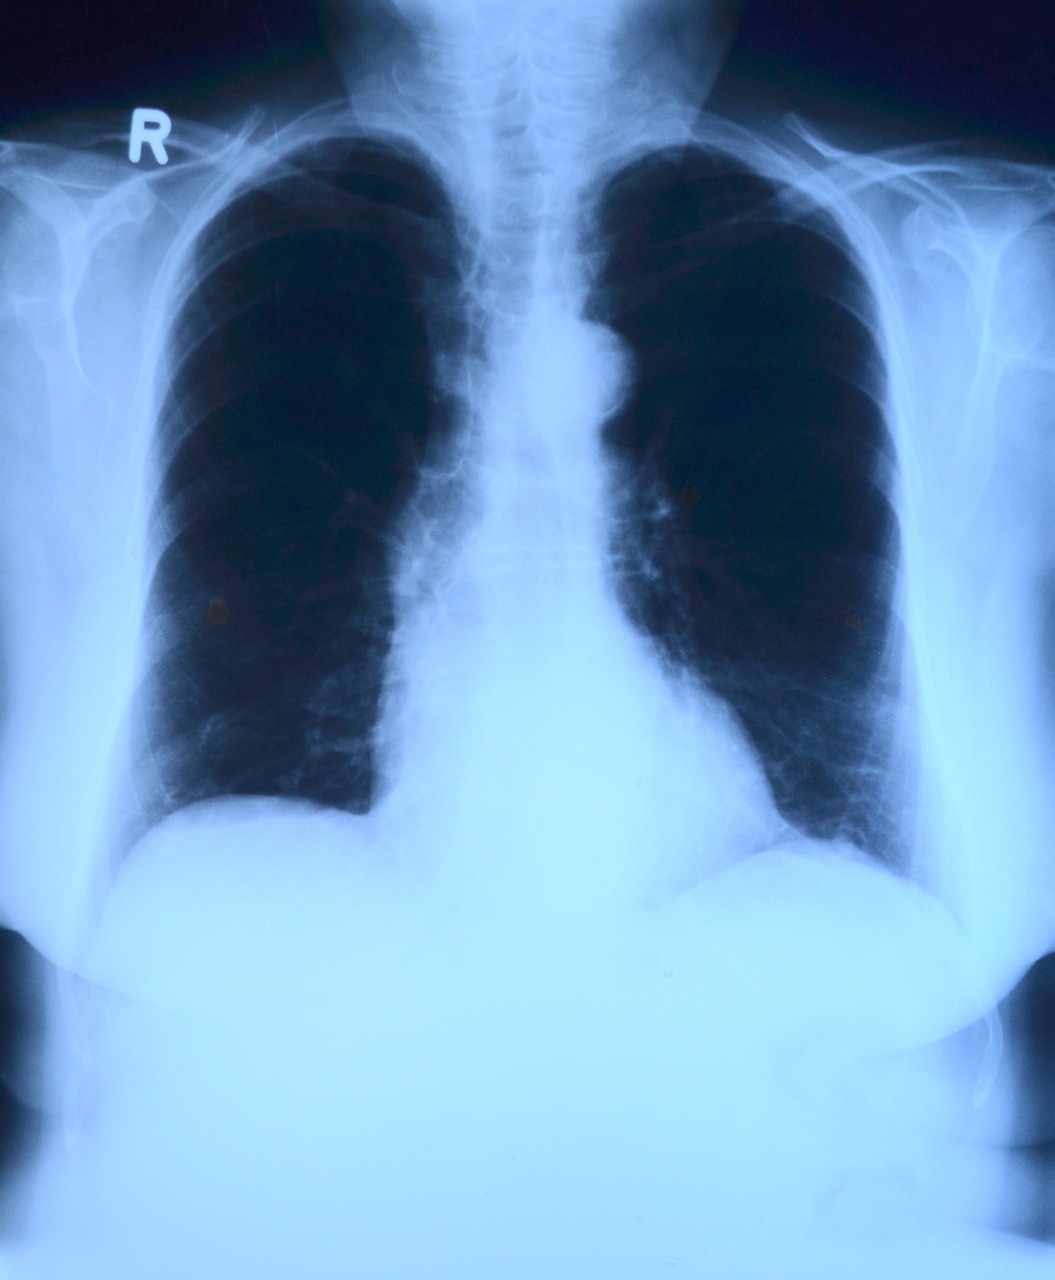

① 흉부 X선 촬영

X선 검사방법으로는 실제 크기로 촬영하는 흉부 직접촬영과 70㎜, 100㎜ 크기의 축소된 사진으로 찍는 간접촬영이 있는데, 여러 사람을 집단으로 검사할 경우에는 간접촬영을 많이 이용합니다.

소견에 따라 초감염 결핵과 재활성화 결핵으로 나뉘며 흔히 전자는 소아 결핵, 후자는 성인 결핵으로 분류하기도 하며 인체면역결핍 바이러스(HIV) 감염자는 초감염 결핵 소견이 주로 나타나는 것으로 알려져 있습니다.

임상적으로 의심은 되나 흉부 X선 검사만으로 결핵의 진단이 힘든 경우에 전산화 단층촬영(CT)이 이용됩니다.

CT는 오래된 섬유화 병변과 새로운 활동성 병변을 구분하는 데 도움을 주는데, 특히 소세기관지나 소세기관지 주위의 병변은 결핵이 시작됨을 특징적으로 보여줍니다

그 외에도 CT는 공동, 흉곽 내 림프절 병증, 좁쌀 결핵(결핵균이 피를 타고 전신으로 퍼져나가 여러 장기에 염증을 일으킨 상태로 마치 좁쌀처럼 미세한 병변이 전신에 나타나는 것), 기관지 확장증, 기관지 협착, 흉막 질환을 진단하는데 민감도가 높고 결핵종 내의 석회침착 여부 판정에 특히 유용합니다.